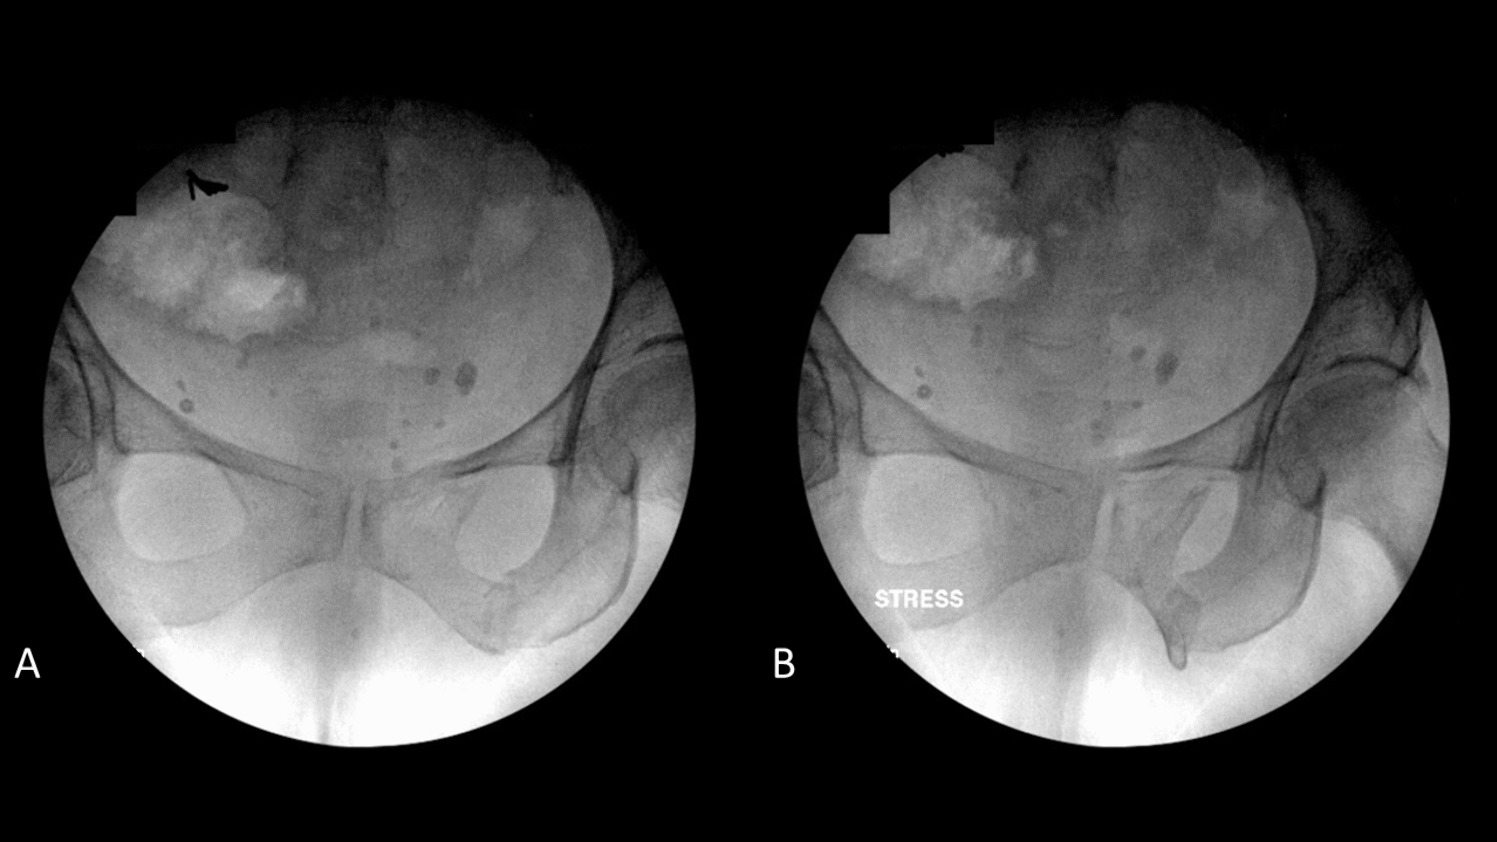

The use and usefulness of stress imaging for guiding treatment decisions for minimally displaced LC injuries with minimally displaced posterior ring injuries are also controversial [1]. Multiple studies have demonstrated that these injuries have low rates of fracture displacement and high rates of union, however when these do occur, they are difficult to treat [11, 12, 4648]. As a result, examination under anesthetic (EUA) was described as a method to identify fractures with occult pelvic ring instability that may be at higher risk for subsequent fracture displacement and/or poor outcomes. Kanakaris and colleagues described the use of an internal rotation stress examine under anesthesia in 40 patients with LC1 pelvis fractures. 23 patients (58%) demonstrated > 2 cm of displacement on fluoroscopic manipulation and were treated with sacroiliac screws in combination with retropubic screws, external fixator or anterior pelvic plating. Tsounidis et al. expanded this series, observing that patients who demonstrated > 2cm displaced and were managed surgically experienced less pain at 72 h, shorter hospital stay, shorter time to pain-free mobilization, and decreased opioid use [49]. Sagi and colleagues independently and concurrently described a more thorough EUA of the pelvis including compression over the trochanters to detect instability to internal rotation forces and a push–pull exam of the lower extremities to detect vertical instability on AP, inlet, and outlet images (Fig. 1) [31]. This group reported that 35% (7/20) of minimally displaced LC1 fractures displaced > 1 cm on fluoroscopy with EUA and were treated with operative fixation.

Fig. 1

(A) Non-stress and (B) stress fluoroscopic images from an examination under anesthesia of a 77-year-old woman with a minimally-displaced LC1 fragility fracture of the pelvis demonstrating gross occult instability

The lateral stress radiograph, an anteroposterior (AP) pelvis radiograph taken in the lateral decubitus position, is an alternative to EUA that avoids many of the above limitations (Fig. 2) [18]. The lateral stress radiograph requires no anesthetic or sedation, can be done in the emergency department by radiologist technicians without physician supervision, and applies a relative standardized force using gravity and the patient’s body weight. Fractures can be objectively measured on the radiograph using the electronic imaging system and compared to standard supine AP pelvis radiographs to determine displacement. In a series of 131 consecutive patients receiving lateral stress radiographs, 62.5% (n = 80) of patients had occult instability, defined as ≥ 1 cm of dynamic displacement [32]. The median age of the cohort was 57 years, 60% were female, and 52% had low-energy mechanisms. Patients with occult instability, compared to those without, were older (63 vs 48 years; p = 0.009), more likely to have parasymphyseal rami fractures (74% vs 48%; p < 0.0001), and rami comminution (96% vs 38%; p < 0.0001). Occult instability had no association with high-energy injury mechanisms, sacral fracture completeness, or sacral fracture comminution. Limitations of the lateral stress radiograph include pain, with some patients being unable to tolerate the lateral position, the potential for malrotated radiographs that can make interpretation difficult, and the difficulty of obtaining in polytraumatized patients with long bone or spine fractures [51].

Fig. 2

(A) AP pelvis radiograph and (B) lateral stress radiograph of the same patient from Fig. 1 redemonstrating the gross occult instability